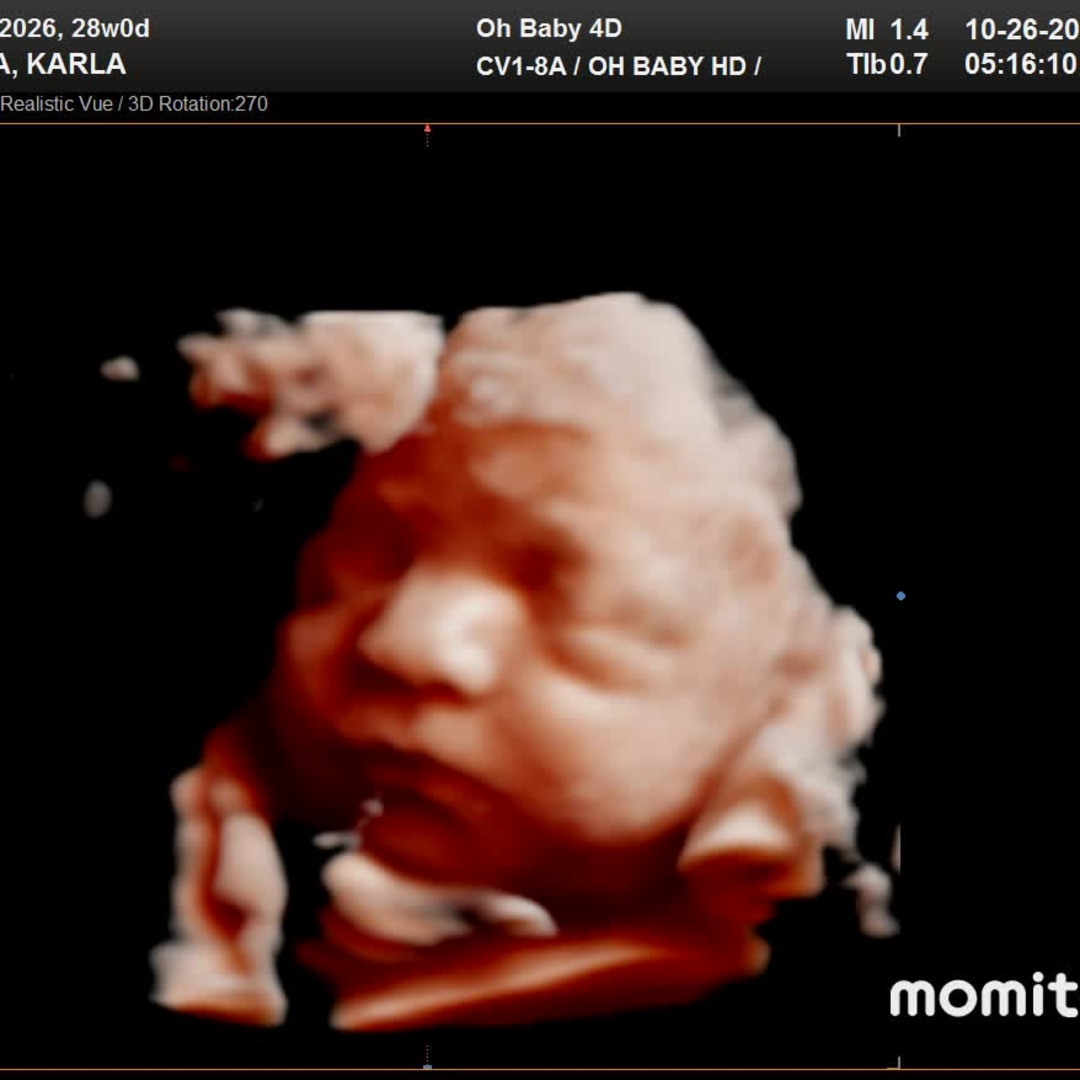

Thank you so much for celebrating baby Mateo with us! We feel incredibly grateful to be surrounded by family and friends who are excited to welcome him into the world. As we prepare for his arrival, we’ve put together a registry with items we thoughtfully chose to help us get started. If you feel moved to give a gift, we would truly appreciate you taking a look there. Your love and support mean more than words.